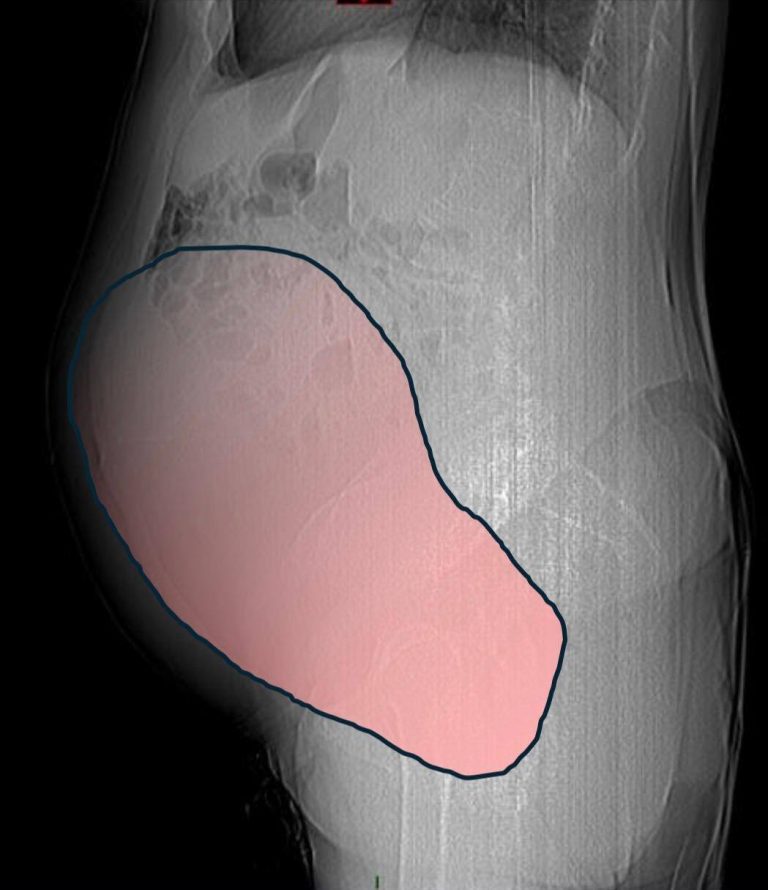

According to NeedToKnow, the surgical procedure lasted for about six hours. During the operation, doctors successfully removed a 28-centimeter tumor that weighed approximately 6 kilograms.

The City of Health and Science of Turin, where the surgery was carried out, described the tumor as being “comparable in volume to a full-term twin pregnancy.”